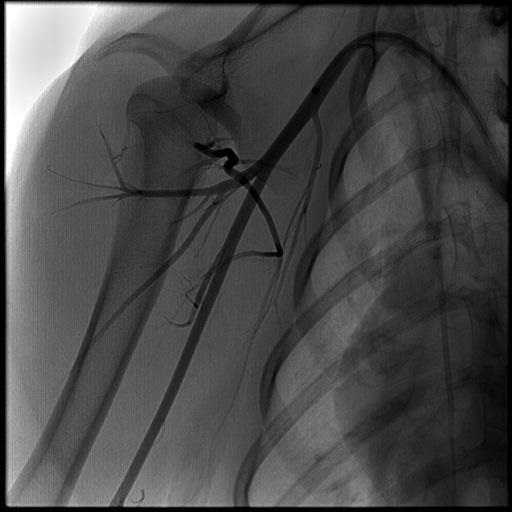

目前已经通过CE Mark,尚没有在美国应用。 MVP-3的临床前研究: 狗的2mm直径的锁骨下动脉,通过0.021“ 微导管进行超选择栓塞

临床研究:放射性栓塞前胰腺动脉栓塞

临床研究:放射性栓塞前,胃右动脉栓塞